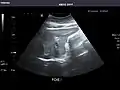

Right kidney

Kidneys: Right and left kidneys measure 11.5 cm and 12 cm in length respectively. No hydronephrosis. Small left lower pole kidney cyst.